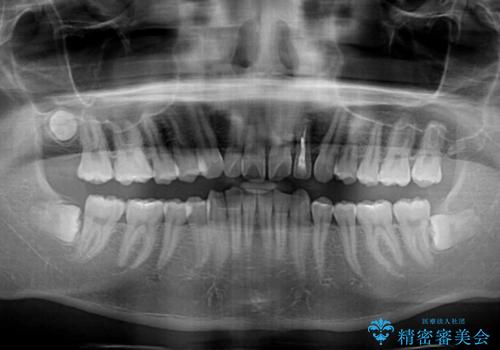

- 深く咬みこみ、前に飛び出した上顎前歯を気にして来院された患者様です。

口元の突出感はあまりありませんでしたが、上顎歯列が全体的に前方にあり、更には下顎歯列が深く咬みこんでいるために、上顎前歯が前方に突出している状態でした。

抜歯は行わず、補助装置を用いて上顎歯列全体を後方移動させ、ワイヤー装置にて奥歯の咬み合わせを改善していくこととしました。